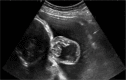

Case description: We present a case of a female patient in utero of 26 gestational weeks with the diagnosis of an occipital encephalocele treated by open fetal surgery. During week 20 of gestation, the diagnosis of occipital encephalocele was made by ultrasound, which was corroborated by fetal magnetic resonance that showed cranial protrusion of neural and meningeal content in the occipital region, measuring 1.6 × 2.8 × 3.3 cm with an approximate volume of 7.7 cc through a bone defect of 6 mm. The closure of the defect was performed by the postnatal surgical technique adapted to the open fetal surgery. Later, the patient was born transabdominal with a 2.8 cm occipital wound, with suture points and approximated borders, normocephalic, without clinical signs of sepsis, hydrocephalus, or overt neurologic compromise.